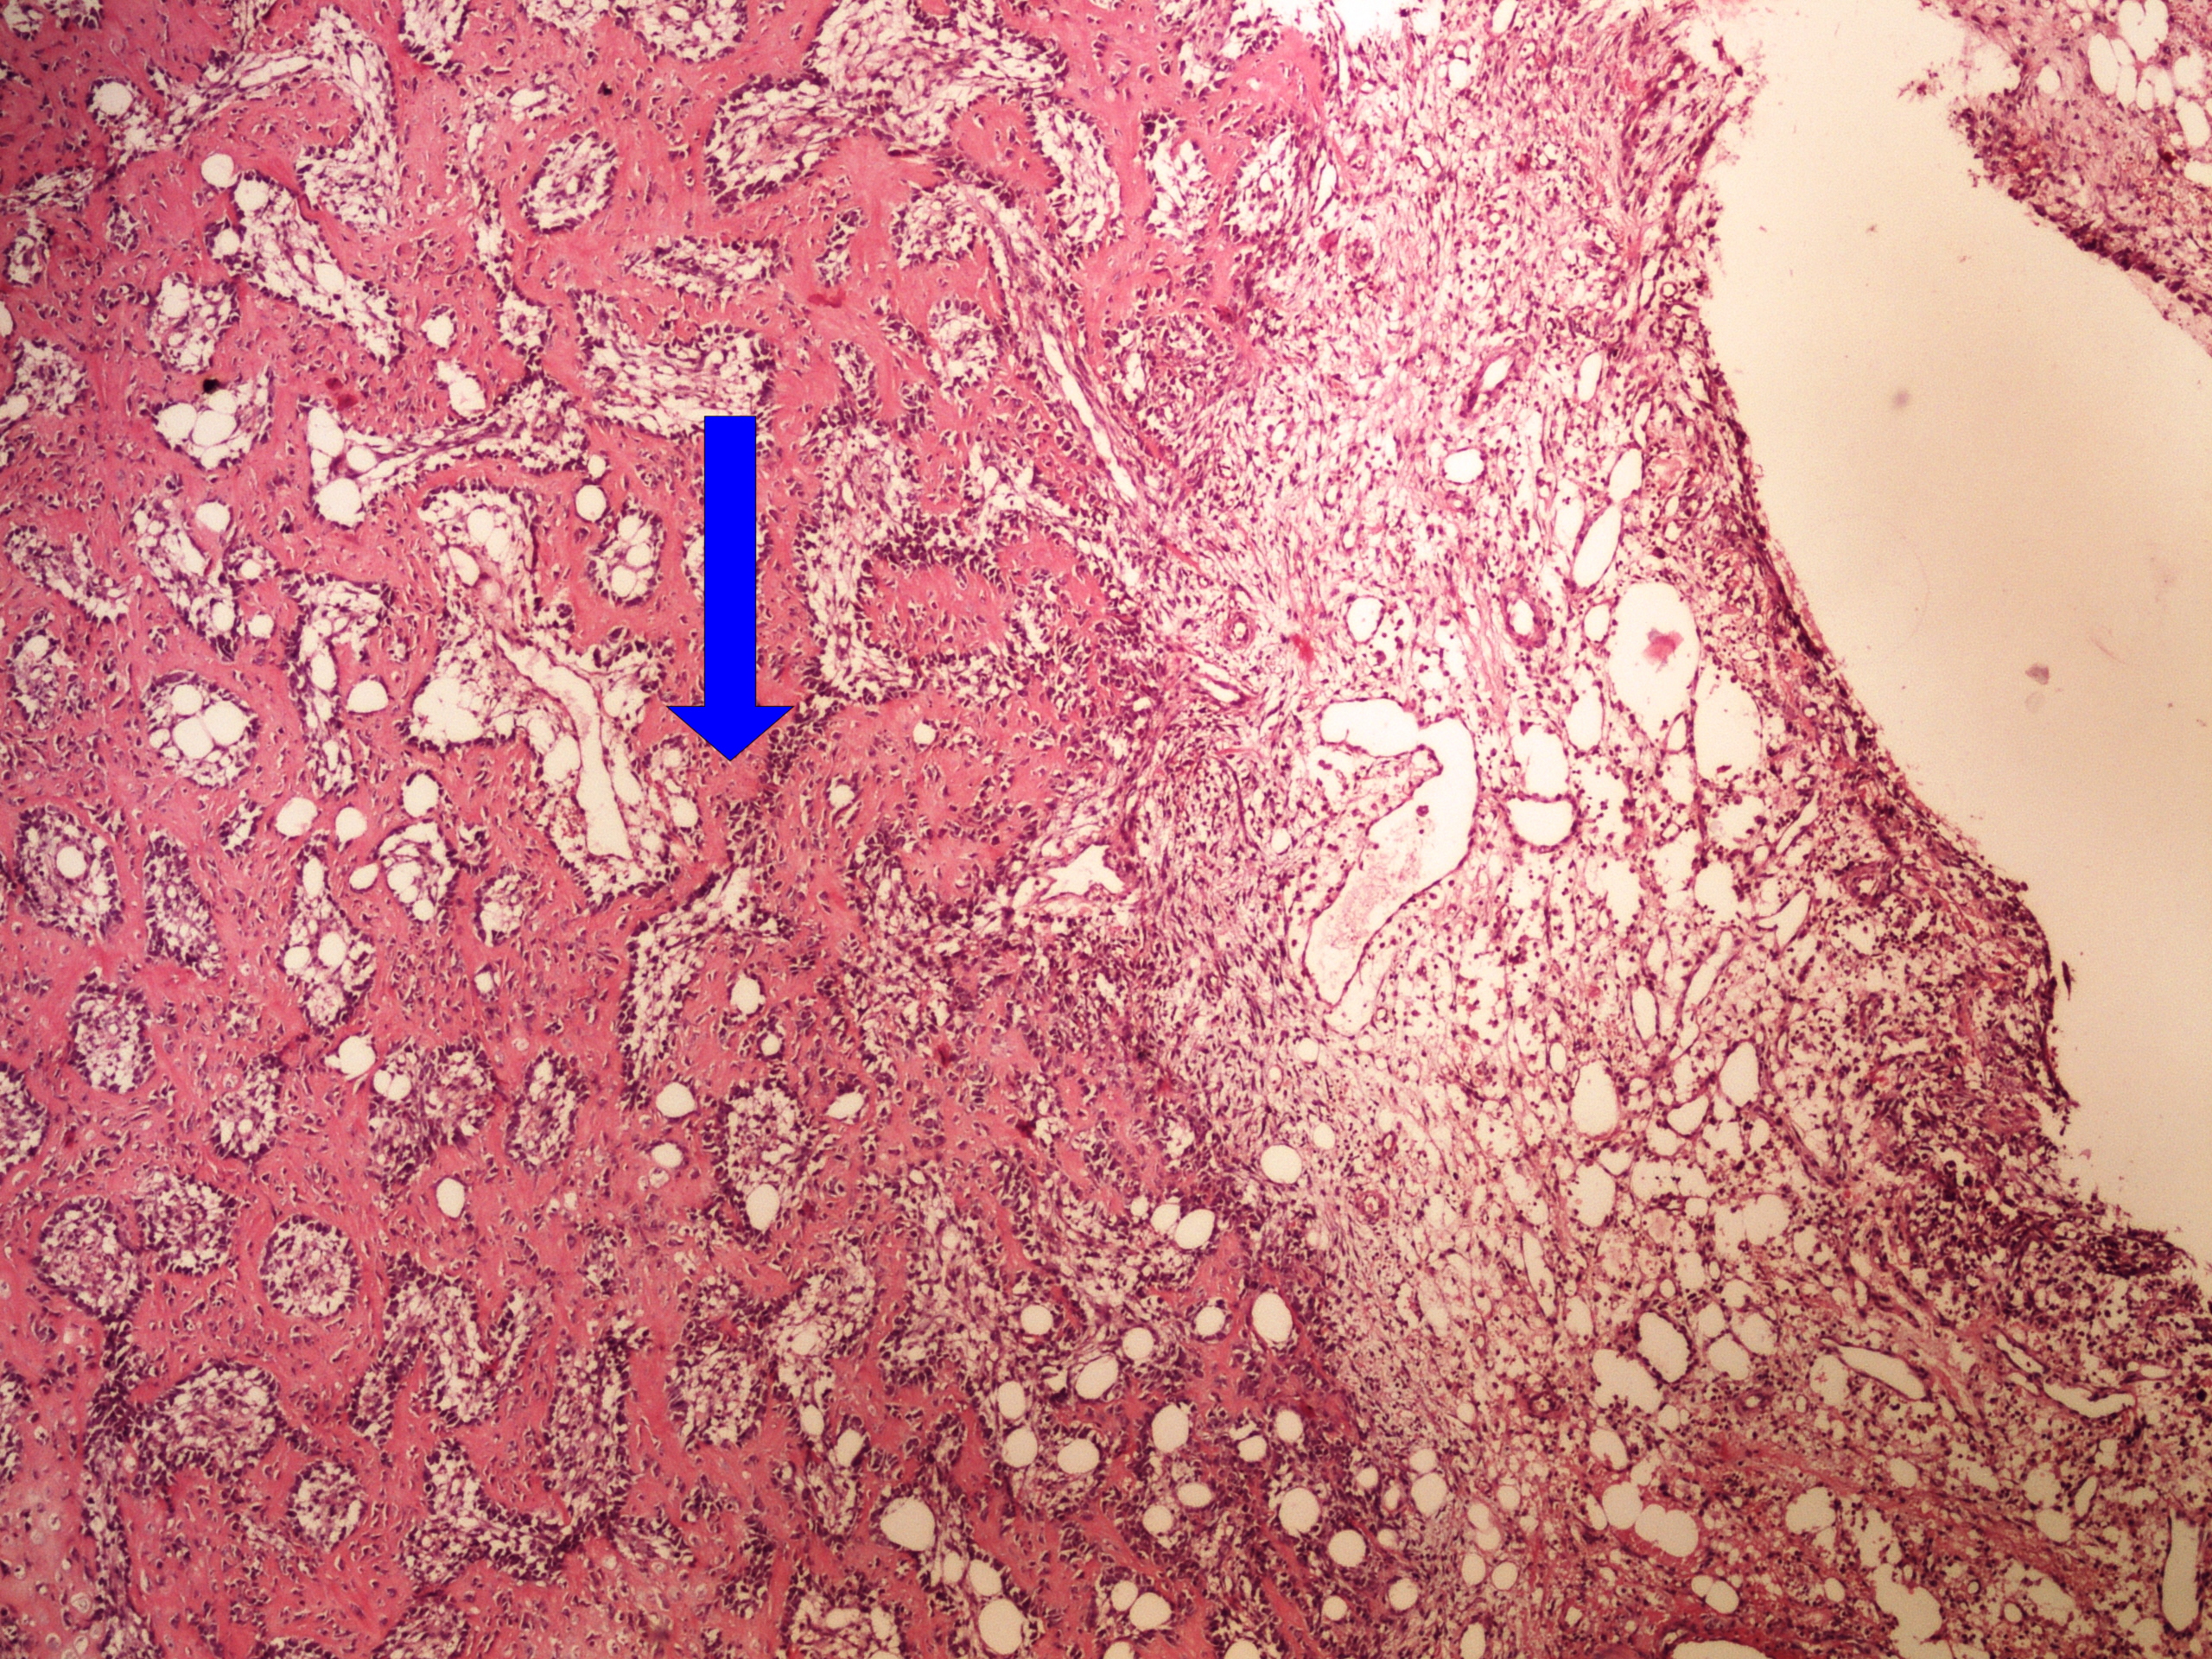

Preparát č.23 a č.24 - miliární TBC plic

Struktury

- miliární uzlík

- vícejaderné buňky Langhansova typu